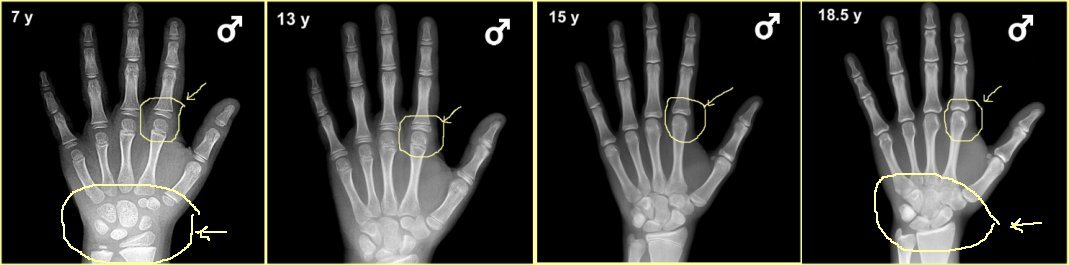

성장판 검사를 통해 성장판이 어느 정도 열려있고, 또 앞으로 얼마의 성장을 보일 것인가에 대한 예측도 중요하겠지만, 성장판 검사의 주 목적은 그 보다는 실제 아이의 나이와 뼈나이, 골연령과의 차이를 보기 위함이 더 큰 것입니다.

또한, 당장의 검사결과수치가 아니라 그 변화과정을 볼 수 있어야하기에 1년에 한 번, 또는 반년에 한 번, 경우에 따라서는 3달마다 검사를 반복하면서 골연령 진행속도를 보면서 성조숙증 여부를 체크할 수 있는 중요한 검사의 하나입니다.